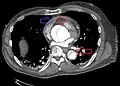

Computed tomography angiography is a fast, non-invasive test that gives an accurate three-dimensional view of the aorta. These images are produced by taking rapid, thin-cut slices of the chest and abdomen, and combining them in the computer to create cross-sectional slices. To delineate the aorta to the accuracy necessary to make the proper diagnosis, an iodinated contrast material is injected into a peripheral vein. Contrast is injected and the scan performed using a bolus tracking method. This type of scan is timed to injection to capture the contrast as it enters the aorta. The scan then follows the contrast as it flows through the vessel. It has a sensitivity of 96 to 100% and a specificity of 96 to 100%. Disadvantages include the need for iodinated contrast material and the inability to diagnose the site of the intimal tear.

-

CT with contrast demonstrating aneurysmal dilation and a dissection of the ascending aorta (type A Stanford) -

Chest CT with descending (type B Stanford) aortic dissection (red circle)

Type A dissection with pericardial effusion as a result.